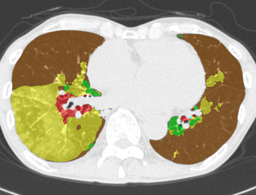

In this paper, we define partial annotation as an annotation format in which only one class is chosen for the annotation and only pixels belonging to the chosen class are annotated per image. For example, in Figure 1(a), although there is ground glass opacity in the image, only consolidation is chosen for annotation and pixels of consolidation are annotated. Partially annotated dataset is less informative for training, however, it is much easier to create compared to fully annotated dataset since annotators only need to focus on one class at a time during the annotation task.

Partially annotated datasets have been utilized previously [8, 9]. In this paper, we propose a new weak supervision technique that fully utilizes partially annotated dataset. Throughout this paper, each DLD pattern is represented or painted in the following colors (CON:cyan, GGO:yellow, HCM:red, EMP:green, NOR:brown.)

Statistics of our dataset are shown in Table 1 and typical images and their annotations for each DLD pattern are shown in Figure 1. In our partially annotated dataset, all the pixels in a slice were manually classified into two classes: dominating DLD pattern and other tissues. In other words, all the pixels in our dataset were assigned one of the labels from either of the two label sets, Lstrong={lCON,lGGO,lHCM,lEMP,lNOR}subscript𝐿𝑠𝑡𝑟𝑜𝑛𝑔subscript𝑙𝐶𝑂𝑁subscript𝑙𝐺𝐺𝑂subscript𝑙𝐻𝐶𝑀subscript𝑙𝐸𝑀𝑃subscript𝑙𝑁𝑂𝑅L_{strong}=\{l_{CON},l_{GGO},l_{HCM},l_{EMP},l_{NOR}\} or Lweak={lCON¯,lGGO¯,lHCM¯,lEMP¯,lNOR¯}subscript𝐿𝑤𝑒𝑎𝑘subscript𝑙¯𝐶𝑂𝑁subscript𝑙¯𝐺𝐺𝑂subscript𝑙¯𝐻𝐶𝑀subscript𝑙¯𝐸𝑀𝑃subscript𝑙¯𝑁𝑂𝑅L_{weak}=\{l_{\overline{CON}},l_{\overline{GGO}},l_{\overline{HCM}},l_{\overline{EMP}},l_{\overline{NOR}}\}. For example, in Figure 1(a), colored pixels were labeled as lCONsubscript𝑙𝐶𝑂𝑁l_{CON} and all the other pixels were labeled as lCON¯subscript𝑙¯𝐶𝑂𝑁l_{\overline{CON}}. In this paper, we call pixels of label lLweak𝑙subscript𝐿𝑤𝑒𝑎𝑘l\in L_{weak} and lLstrong𝑙subscript𝐿𝑠𝑡𝑟𝑜𝑛𝑔l\in L_{strong} as weakly annotated pixels and strongly annotated pixels respectively. Our pixel-wise annotations were created in the following steps. First, up to 3 slices were chosen for the annotation for each HRCT scan and for each slice, one representing DLD pattern was chosen by a radiologist. Second, three radiologists performed pixel-wise binary annotation (e.g. binary annotation between lCONsubscript𝑙𝐶𝑂𝑁l_{CON} or lCON¯subscript𝑙¯𝐶𝑂𝑁l_{\overline{CON}}) for each slice. Finally, the radiologists’ annotations were merged by taking majority classes for each pixel (i.e. pixels labeled as a DLD pattern by more than 2 radiologists became the corresponding DLD pixel). In addition to the DLDs annotation, lung fields were manually segmented under the supervision of radiologists and training and testing were conducted only within the lung fields.

Figure 1: Typical slices for each DLD classes. Slices of HRCT are shown in lung window setting (window-center=-600, window-width=1500) with annotated labels superimposed in transparent colors. Note that even if more than one DLD patterns existed, only one DLD pattern was chosen and annotated for a slice to facilitate the annotation process.